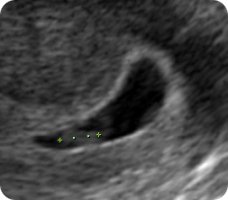

Ултразвук

Ултразвучниот преглед во 6. недела опфаќа приказ на матката, мерење на должината на ембрионот (CRL) и мерење на жолчната кеса (Yolk sac). На сликите е прикажано и жолтото тело кое настанува од прснатиот фоликул во јајникот и кое има хормонска улога во одржување на бременоста. Должината на ембрионот (CRL) во овој период изнесува околу 5,5 mm.